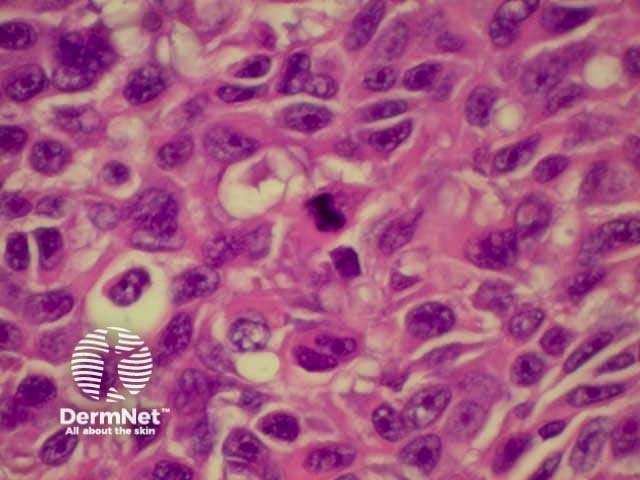

SCC is characterised by proliferation of irregular nests of abnormal squamous cells arising from the epidermis and invading the dermis. Tumours are traditionally divided into well, moderately or poorly differentiated tumours by a subjective assessment of how significantly the tumour cells differ from normal keratinocytes. In general, the greater the degree of keratinization, the better differentiated the tumour is thought to be. Except in the case of very poorly differentiated tumours, this does not have a great bearing on prognosis. More important is the depth and irregularity of invasion, particularly the presence of perineural infiltration, which is associated with a much higher rate of recurrence if not widely excised. The site of the lesion is also important; tumours of the lips and ears have a considerably higher rate of metastasis to lymph nodes.

There are several descriptive variants of SCC including spindle cell SCC and acantholytic (or adenoid or pseudoglandular SCC). These mainly are of note due to the difficulty of diagnosing the tumour as SCC, but they may also imply a slightly worse prognosis. A further rare variant is verrucous carcinoma, a lesion in which the histology has a deceptively benign appearance in that there is very little cytological abnormality. Diagnosis in these cases may be delayed and the diagnosis may not be made until several biopsies have been performed. These tumours recur locally, but do not generally metastasise.

From the above comments it can be seen that the histological features of SCCs can vary, but in general are:

Pathology of SCC Pathology of SCC Pathology of SCC Pathology of SCC